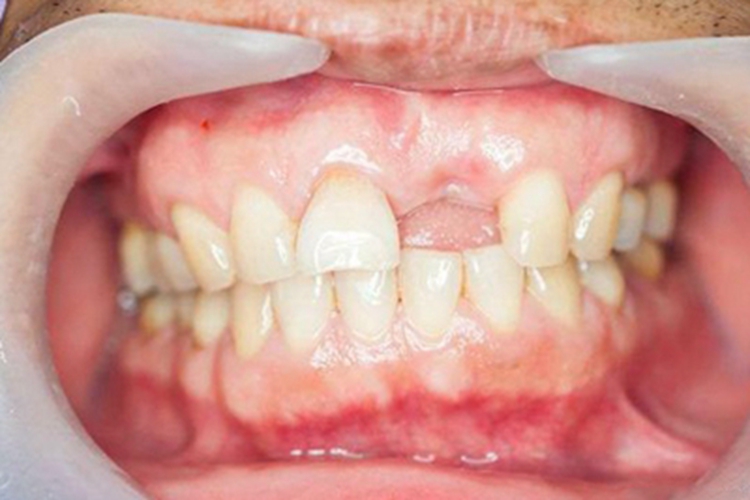

牙龈萎缩可发生于全口牙龈,临床上可表现为牙龈缺血、水肿,颜色发白。牙龈高低不协调,伴随局部肿胀,自觉牙龈敏感等症状,随疾病发展,影响美观,并出现根面龋,部分患者还伴随着牙齿缺失的症状。

患者继发牙周炎、刷牙不当、固定修复体位于龈下过深等情况,都可导致牙结石、牙菌斑等,若长期得不到清理,引发细菌滋生,刺激牙龈,就会导致牙龈萎缩,进而出现牙龈颜色发白缺血的症状。